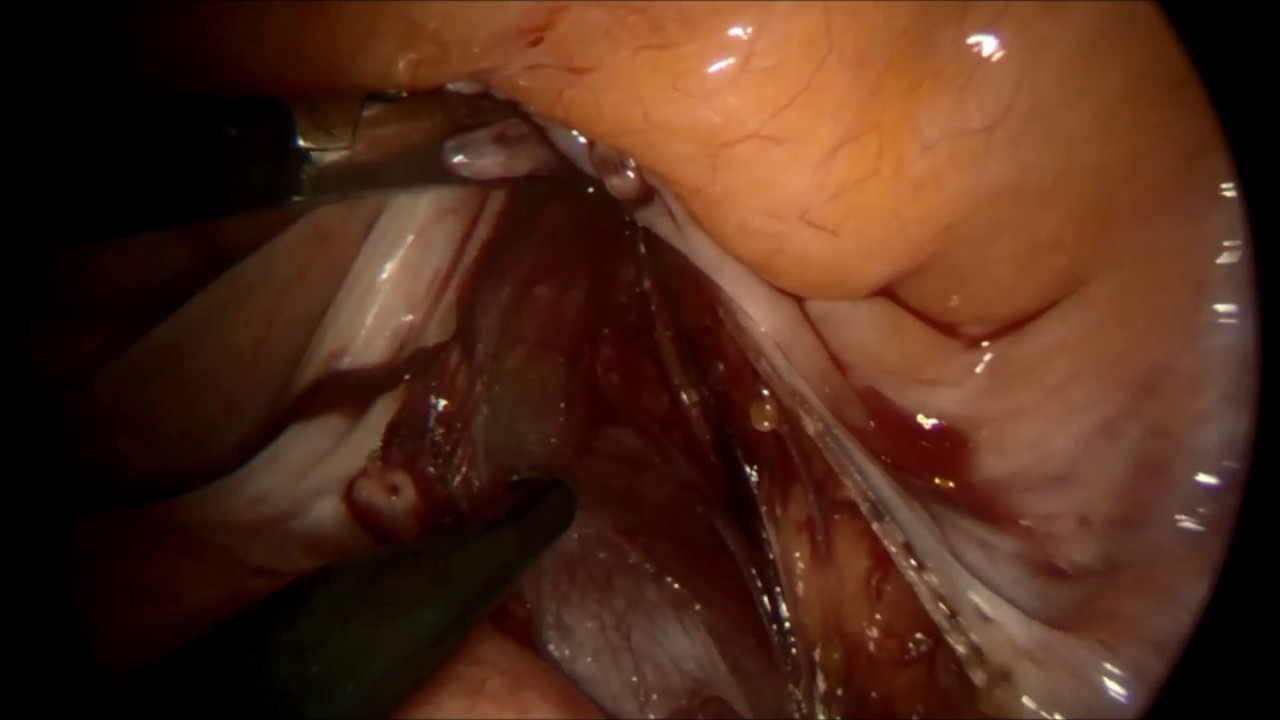

Laparoskopi

Gevher Nesibe Mahallesi Gök Geçidi No: 15 Kocasinan, 38070 Melikgazi, Kayseri

System Hospital Tüp bebek merkezi

Laparoskopik Cerrahi

Laparoskopik Ektopik Gebelik Ameliyatı